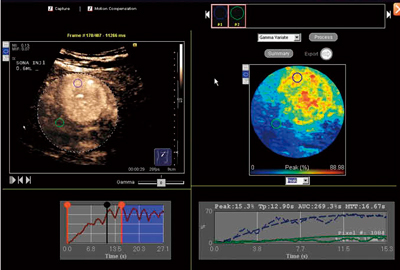

造影エコーのビジュアル的評価に,定量的評価を加えるためのアプリケーションである。造影エコーの動画像を取り込んだ後で,領域ごとの輝度の違いを測定したり,輝度の時間変動のグラフを描くことができる。さらに,最大輝度,最大輝度に至る時間,時間輝度曲線の時間積分値をカラーコード化したパラメトリックイメージの表示が可能である(図5)。

図5 パラメトリックイメージの例

転移性肝がん。腫瘍を取り巻く血管構造が明瞭に表示された。

(画像ご提供:兵庫医科大学・飯島尋子先生)